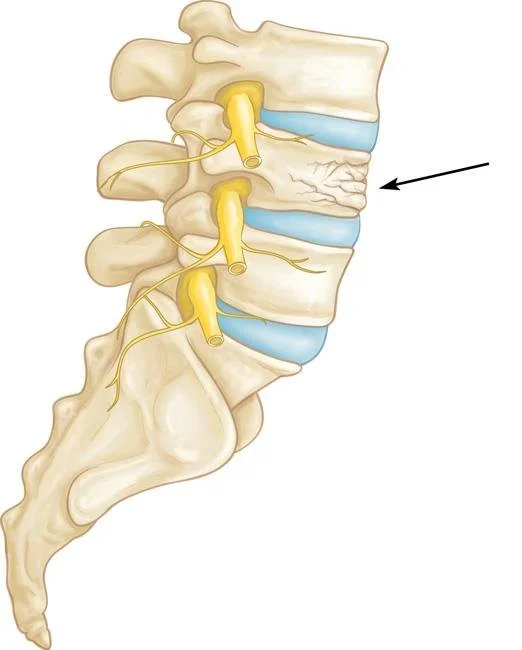

Chiros are the only professionals I am aware of that use the terminology “adjustment”. While they are adjusting your body, this can be misleading (just like MRIs) and can cause people to think their bones are out of place or their hip or disc may literally pop out of its place. I have had multiple patients tell me their biggest fear is that their spine will crumble after getting MRI results or seeing chiro. None of this is possible unless you have an extremely advanced, rare bone eating cancer in your spine. The body is a miraculous healing machine even with osteoporosis and stress fractures in the spine that heal on their own (pictured). I have heard not so good thoughts when I have asked patients what their biggest fear is (which takes us down a rabbit hole of pain science I will not go down in this blog). I have spent far too much time in my office de-catastrophizing verbiage and jargon other professionals have used. We have to be careful with our words because they can cause harm too.